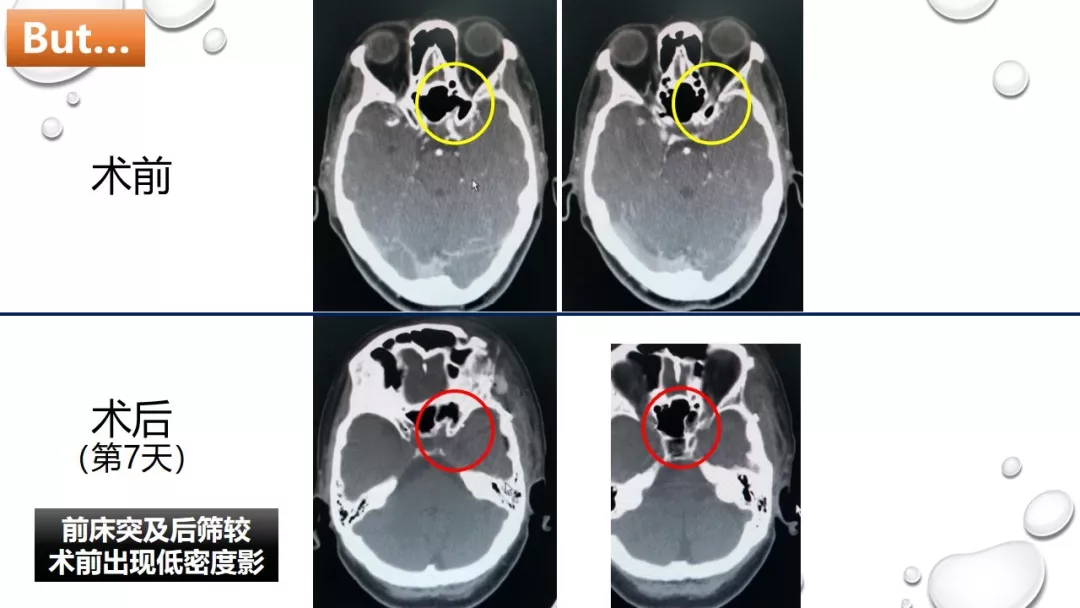

今日与大家分享的是《正海-妙术视界》第一百三十二期,由唐都医院神经外科赵天智、郭为、贺世明、屈延、高国栋带来的精彩手术:“前床突磨除与脑脊液漏处理---中鼻道经筛入路解剖、阅片与手术”,欢迎观看、分享。

前床突磨除